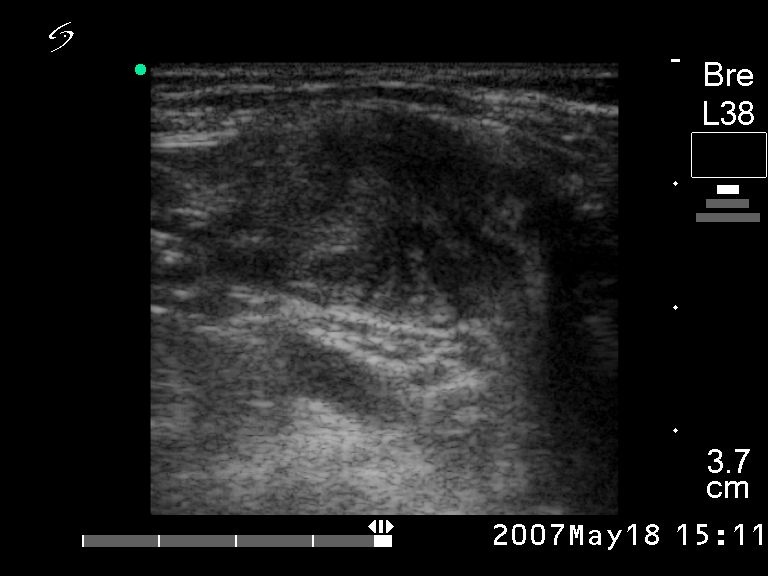

Ultrasonography. There was a hypoechogenic nodule in the right lobe while multiple hypoechogenic lesions were detected in the right side of the neck.